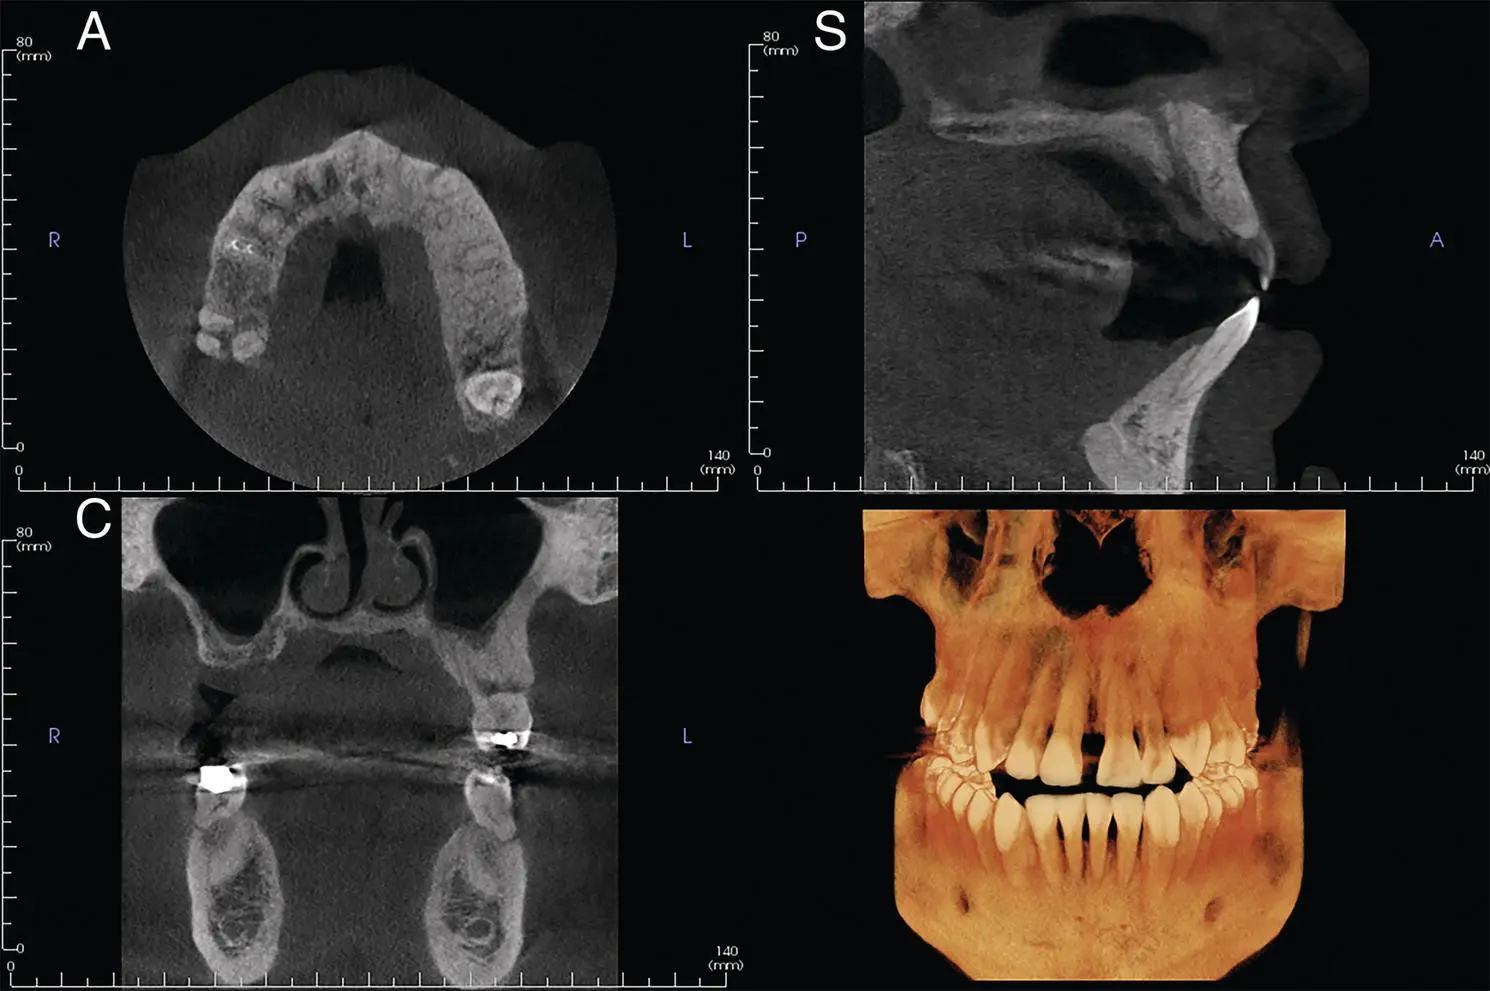

Figure 1.2.Axial (A), coronal (C), sagittal (S), and reconstructed 3D views from a small FOV.